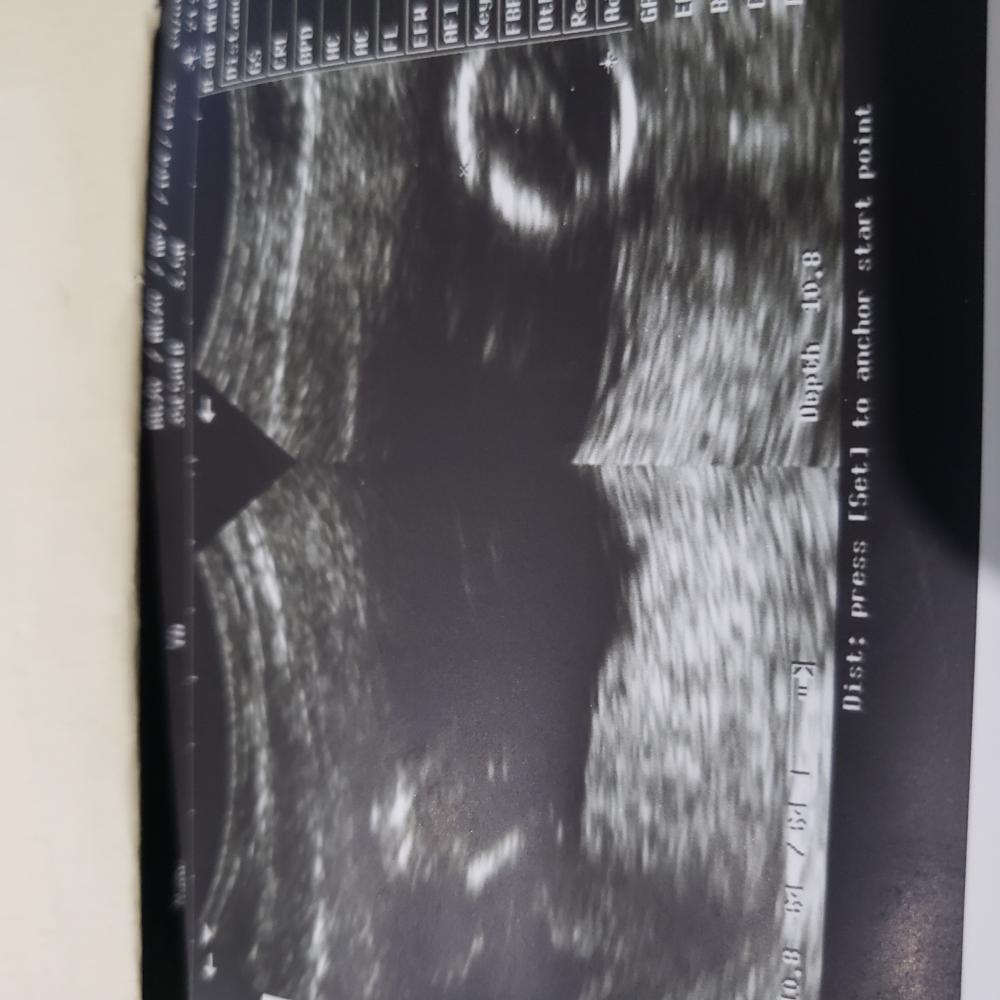

انا في الاسبوع ١٤ ورحت اليوم عملت سونار وقالت لي الدكتوره مش مبين ولما اصريت تحاول قالت لي انها ماتحب تجيب احتمالات ارجع بعد شهر ونص ويكون واضح ونعرف جنسه

بس ايش يصبرني شهر ونص متحمسه اعرف😅

ياريت الي تعرف في السونار تشوف ايش مبين معها🌹

سلام بنات انا في الاسبوع ١٤ ورحت اليوم عملت سونار وقالت لي الدكتوره مش مبين ولما اصريت تحاول قالت لي انها ماتحب تجيب احتمالات ارجع بعد شهر ونص ويكون واضح ونعرف جنسه بس ايش يصبرني شهر ونص متحمسه اعرف😅 ياريت الي تعرف في السونار تشوف ايش مبين معها🌹